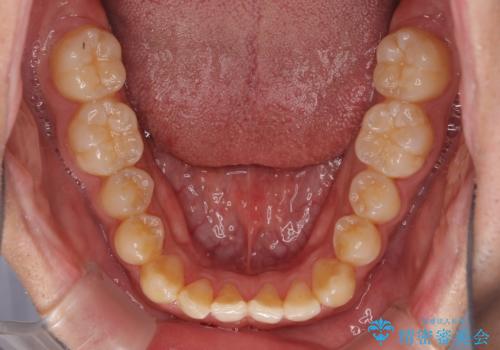

下顎前歯と上顎の部分矯正

- 上下の前歯の叢生を気にして来院された患者様です。

前歯のみの矯正治療を希望でしたが、上顎臼歯が舌側転位していたため、上顎は全体を、下顎は前歯のみを矯正治療することとしました。

矯正治療は上下全顎を行うことが大前提ですが、費用などの点から、今回は部分矯正を選択することとなりました。

患者様本人は咬みにくさを感じていないようですが、部分矯正は咬み合わせの改善が困難であることが多く、咬みにくさが残ることがあります。